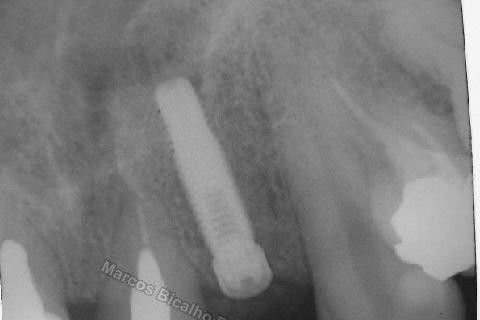

Este caso tem o objetivo de demonstração da técnica que normalmente sigo ; em casos onde ocorre fratura da raiz e consequentemente abscessos, com ou sem formação de fístula. Neste caso fiz a exodontia com preenchimento do alvéolo com biomaterial (osso bovino liofilizado + coágulo do paciente). Após 90 dias, mais ou menos, instalei o implante. Esperei mais 4 meses e realizei ontem (12/11/2010) a instalação do cicatrizador com o cuidado de preservar tecido mole, sem remoção de material, apenas afastando gengiva e "enrolando" a sobra de mucosa em direção a face vestibular, para promover conservação de papila futuramente. Se ocorrer excesso de papila, sem problema, remove-se um pouco, mas a intenção é não deixar faltar, o que resultaria em indicação para enxertos gengivais.